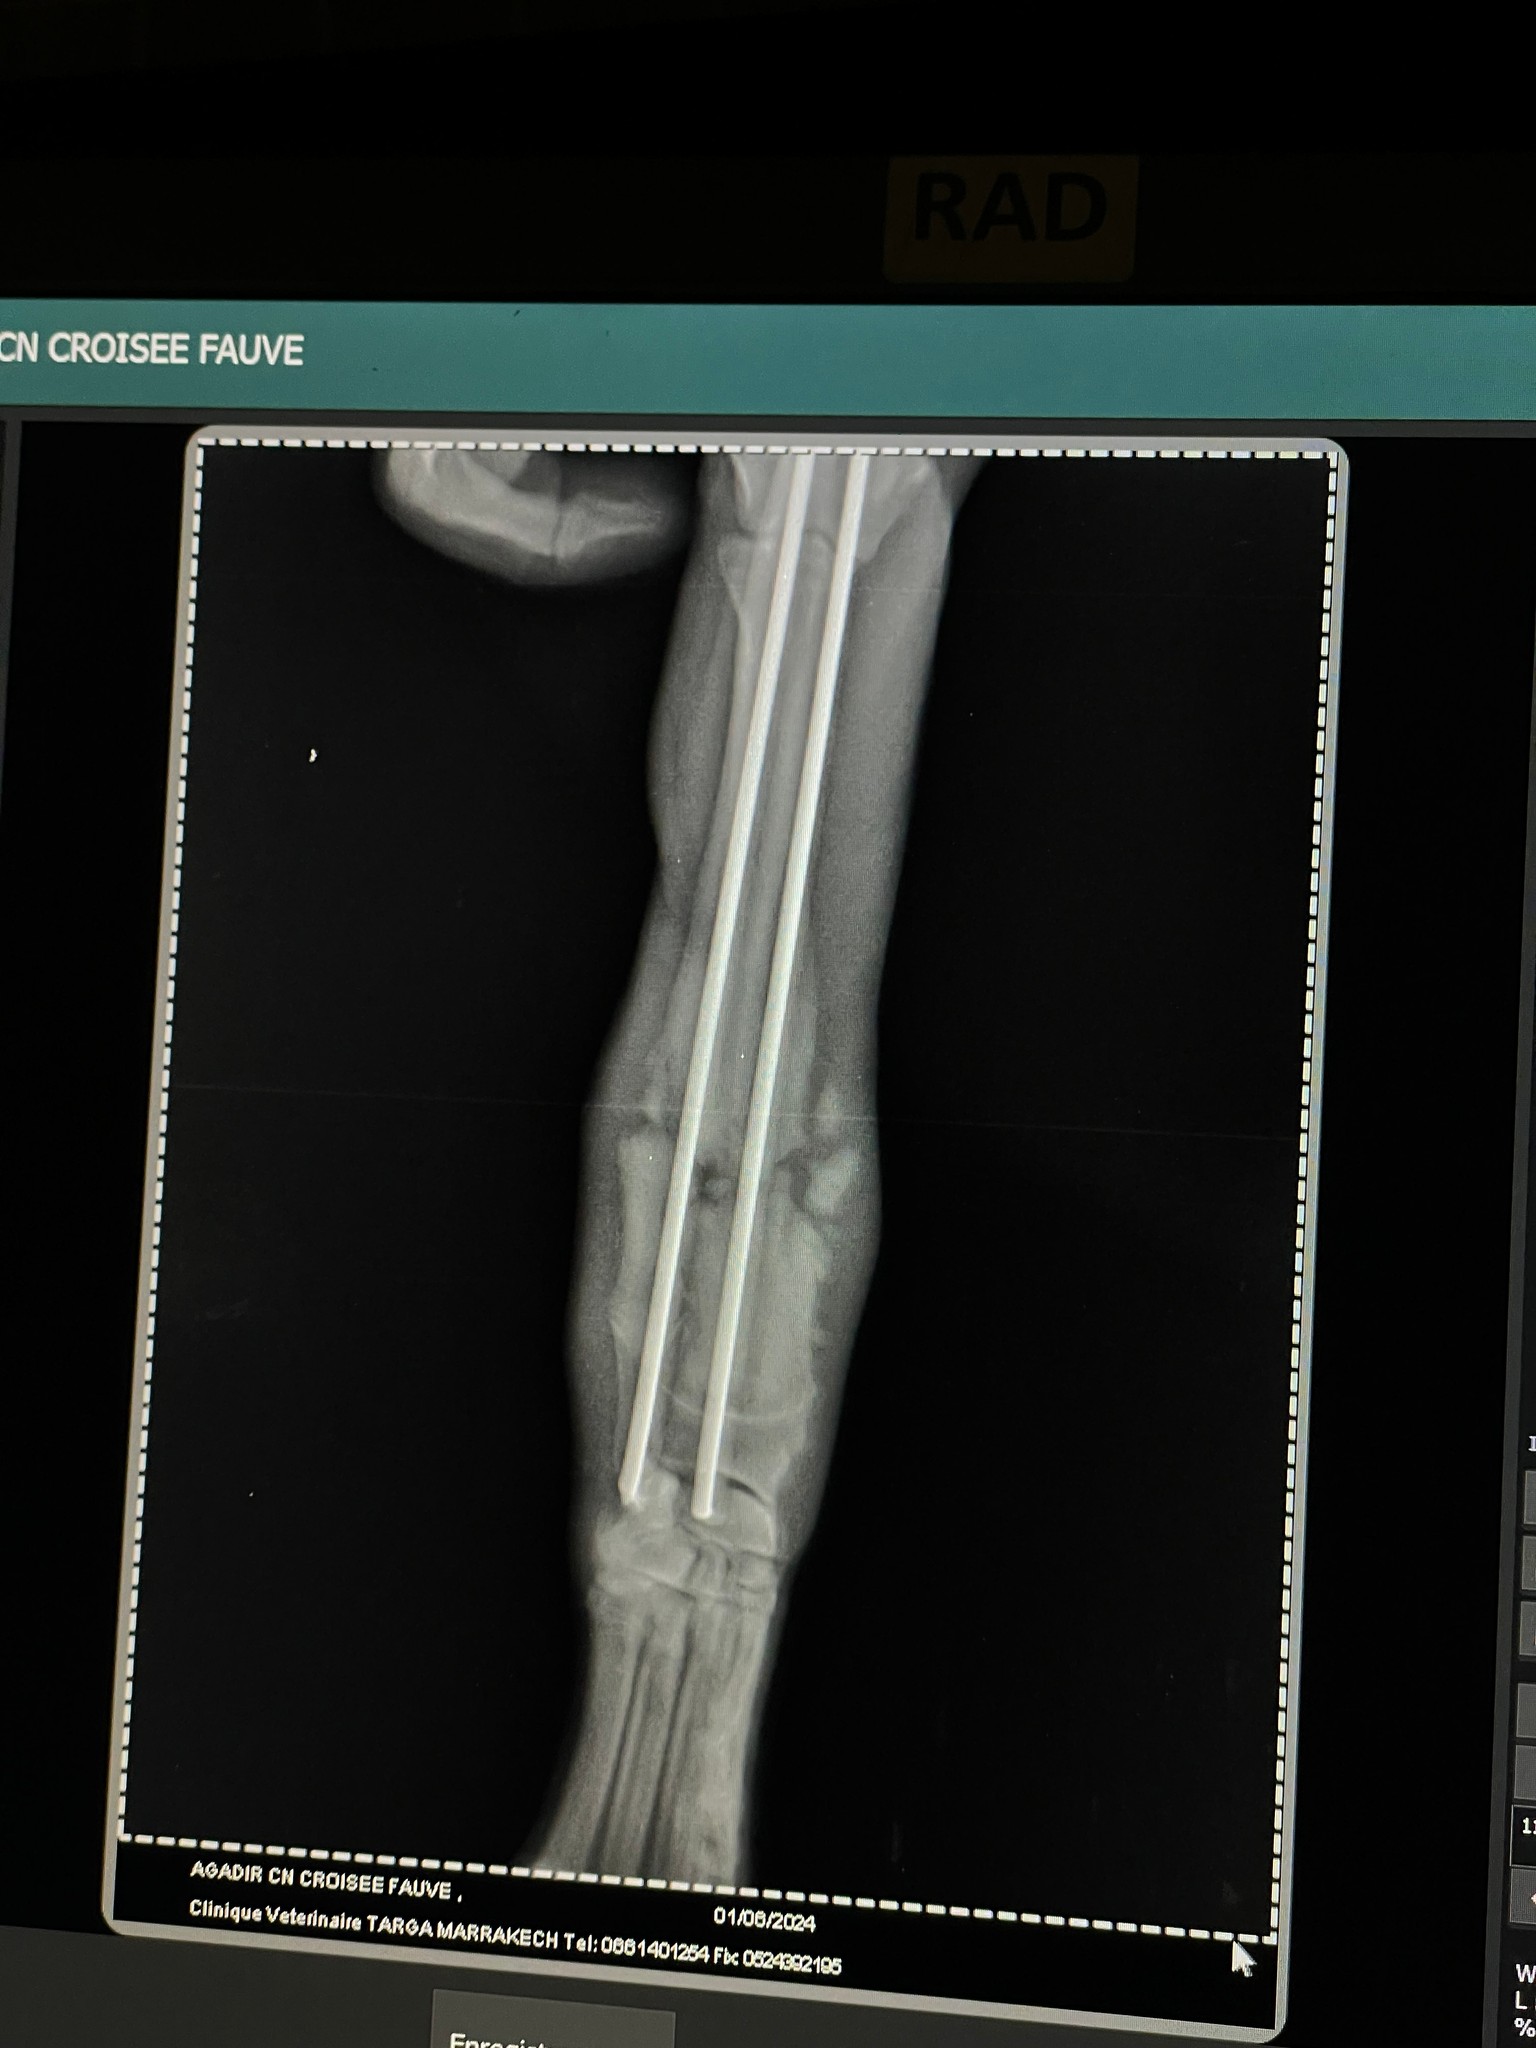

Wir haben voller Hoffnung gewartet mit der Publikation glaubten aber fast nicht daran! Beni wurde verunfallt in Bensergao Marokko gefunden mehr tot als lebendig. Die Vorderbeine waren ganz offensichtlich gebrochen und da sie die Hinterbeine nicht bewegte war das Rückgrat sicher auch beschädigt. Trotzdem zeigte sie ganz kleine Bewegungen und der Schwanz wedelte ebenfalls ganz leicht. Vorsichtig wurde sie geborgen und auf die Ferme gebracht. Dort zeigte sie ganz klar ihre Lebensfreude und den Willen, weiterleben zu wollen. Gestern wurde sie nun nach Marrakkesh gebracht und die Vorderbeine operiert. Drücken wir ihr ganz ganz fest die Daumen und Pfoten, dass auch ihr Rückgrat langsam wieder heilt und sie wieder laufen lernt. Helft ihr mit, die Kosten für sie zu tragen?